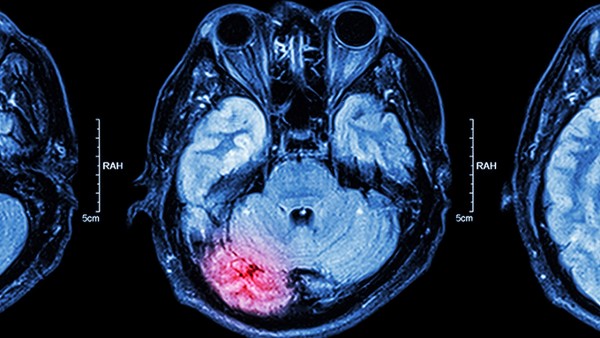

脑梗死一般是指缺血性脑卒中。通常情况下,缺血性脑卒中需要和短暂性脑缺血发作、颅内肿瘤等疾病进行鉴别。

1.颅内肿瘤:颅内肿瘤是指原发于颅内的肿瘤以及从身体其他部位转移过来的恶性肿瘤,由于肿瘤细胞会压迫到周围的神经组织,从而引起一系列的症状,如头痛、头晕、恶心、呕吐等。对于体积较小的良性肿瘤,可以通过手术切除的方式进行治疗,而对于体积较大的恶性肿瘤,则需要通过放疗、化疗等方式联合治疗。